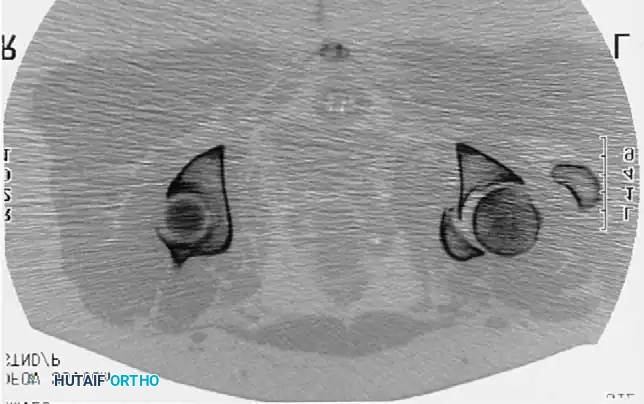

Fig. 53-4 Anteroposterior pelvic radiograph ( A ) and CT scan ( B ) of irreducible hip dislocation with posterior wall acetabular fracture. Posterior wall fragment is incarcerated, blocking reduction.

If closed reduction under conscious sedation or general anesthesia fails, urgent open reduction is mandated. A rapid, fine-cut (2-3 mm) Computed Tomography (CT) scan should be obtained to identify the incarcerating fragment—often a rotated posterior wall fragment or an intra-articular osteochondral loose body. Prolonged dislocation exponentially increases the risk of femoral head osteonecrosis and irreversible sciatic nerve ischemia.